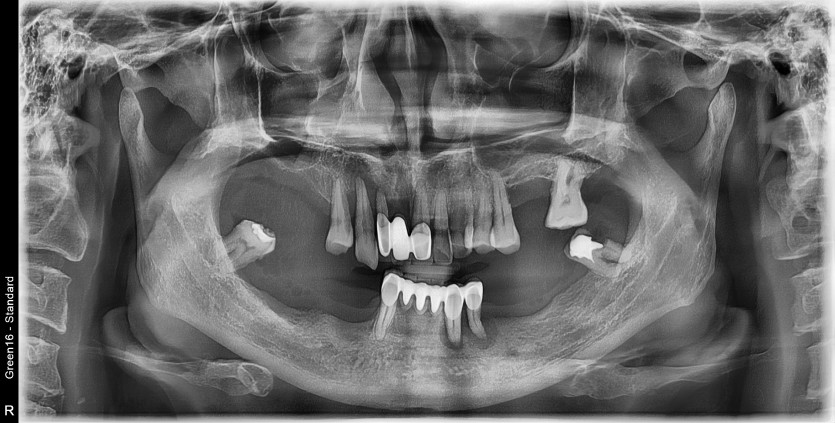

만 58세 전체 임플란트 증례

전체 임플란트 증례입니다.

18개의 임플란트로 완성하였습니다.